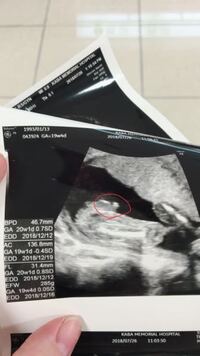

3人目妊娠中です 三本線が見えるので女の子だと思います とエコーを Yahoo 知恵袋